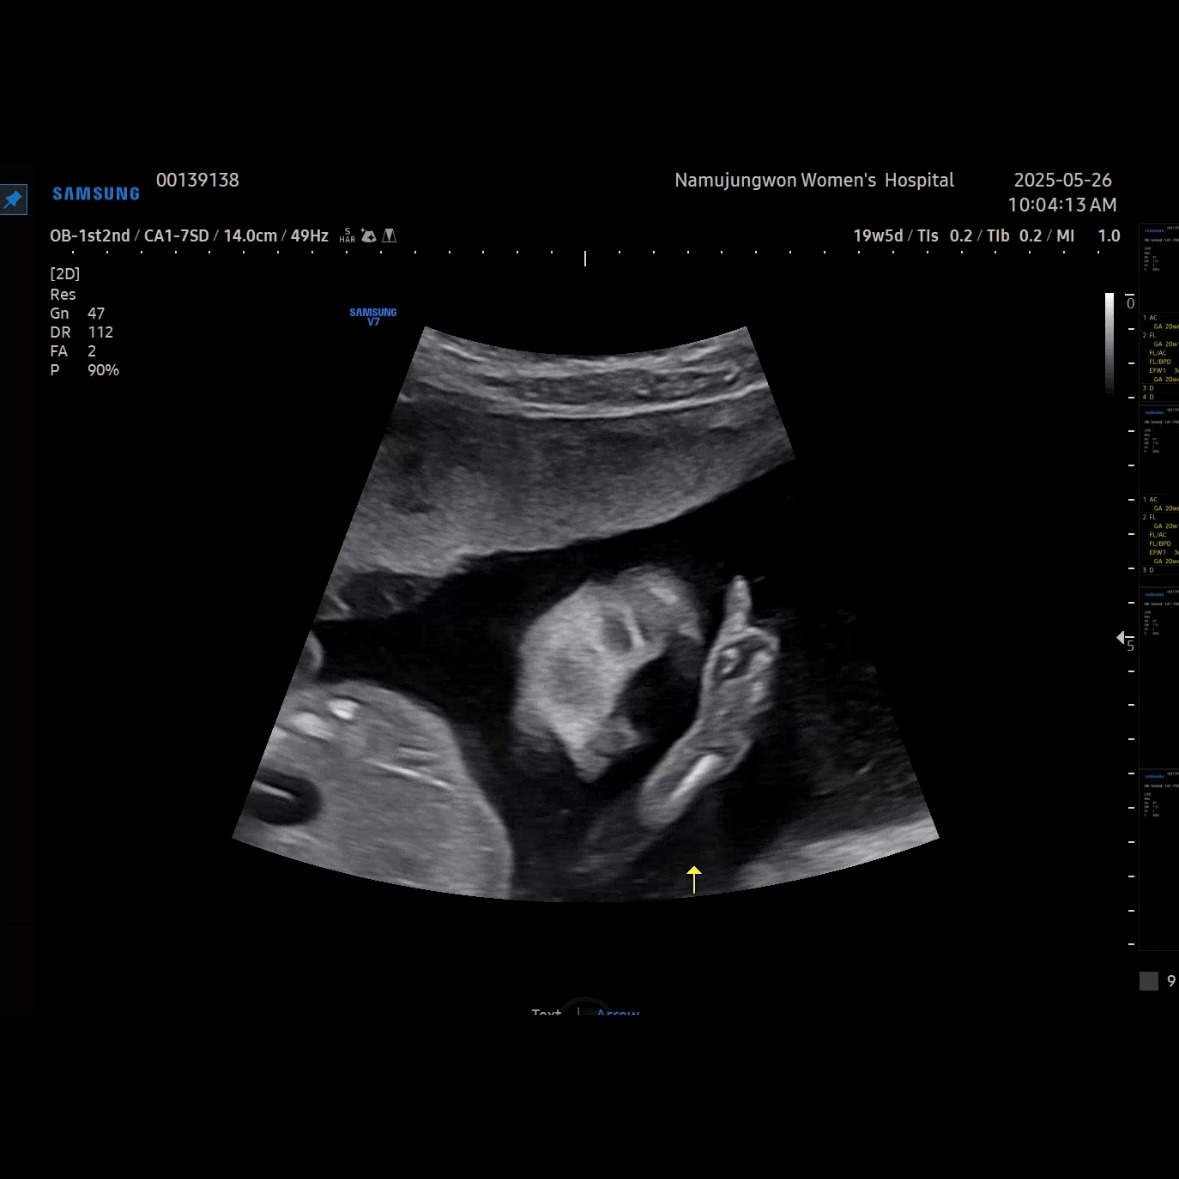

유민이 19주 5일 차에 보러 간 초음파

초음파를 보면 머리둘레, 배둘레, 허벅지 뼈길이를 꼭 재보는 데 유민이는 갈 때마다 1주 정도씩 평균보다 크게 측정된다. 1-2주 크기차이는 의미 없다고 괜찮다고 했다.

이제 얼굴이 형태가 많이 보인다. 코랑 입 위주로 보여줬다. 눈 쪽으로는 손을 올리고 있었다. 이렇게 보면 장기나 뇌나 얼굴이나 대부분 만들어져서 꽤 클 것 같이 생각되지만, 아직까지 400g이 안 되는 무게였다.